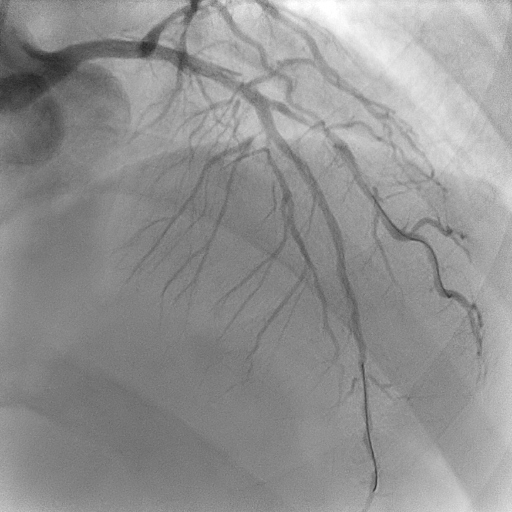

Mid–proximal LAD was sequentially prepared with SC 2.0 balloon and IVUS guidance; distal LAD underwent POBA with SC 1.5 balloon. Lesions in mid LAD and proximal LAD were refined with scoring balloons 2.5/15 and 3.5/15, respectively, treated with DCBs 2.5/30, 2.5/30 and3.5/25. A proximal Type C dissection sealed with a Fantom Encore BRS 3.0/24, post-dilated with NC 3.5/15. LCx and OM prepared with sequential SC balloons 1.5/15 and 2.0/15. Treated with DCBs 2.0/20 at proximal OM and 2.0/30 at LCx. RCA planned for staged angioplasty. Left coronaries were restudied at the time when patient was readmitted for staged angioplasty to RCA, showed excellent results. RCA prepared with POBA to the PL branch with 1.5 SC balloon, scoring balloon 2.5/15 to distal–mid RCA, followed by DCBs 2.75/40 and 3.0/30. A Type A dissection ensued in mid RCA, yet final TIMI III flow achieved.

The Fantom Encore, a third-generation bioresorbable scaffold, exemplifies the principles of coronary rejuvenation by providing transient arterial support before fully resorbing, thereby preserving natural vasomotion and avoiding the long-term liabilities of permanent metallic implants. In this case, it served as an elegant bail-out for a DCB-related dissection, maintaining the philosophy of the ¡°leave nothing behind¡±. Its radiopaque Tyrocore polymer affords fluoroscopic visibility, enhancing procedural precision and ease of usability. The combined use of DCB and BRS delivered an exquisitely refined final angiographic result, underscoring the pursuit of true coronary aesthetics.